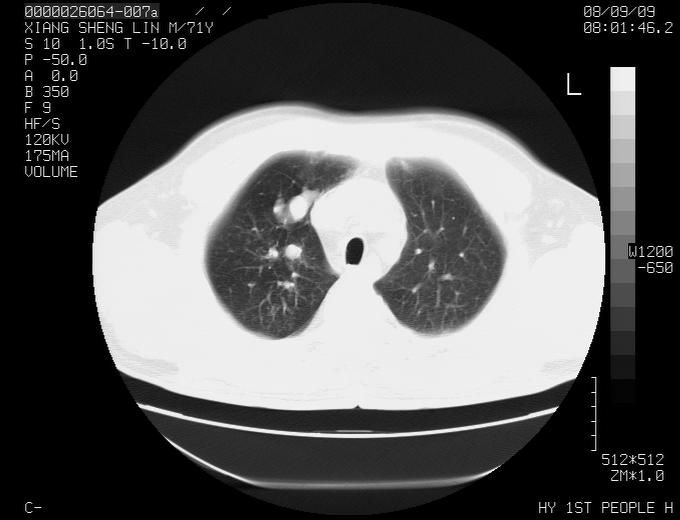

标题: CT15869:男性,71岁,因咳嗽而就诊,请讨论右上肺病变性质 [打印本页]

标题: CT15869:男性,71岁,因咳嗽而就诊,请讨论右上肺病变性质

患者,男性,71岁,因咳嗽而就诊,

典型的右肺中心性肺癌并纵隔淋巴结转移

病灶中等程度强化 还是支持肺癌诊断

考虑右肺中心性肺癌并右肺门及纵隔淋巴结转移。

1,右肺中心型ca,气管隆突旁淋巴结转移。

2,右膈明显抬高,建议肝脏扫描排除转移或原发灶。